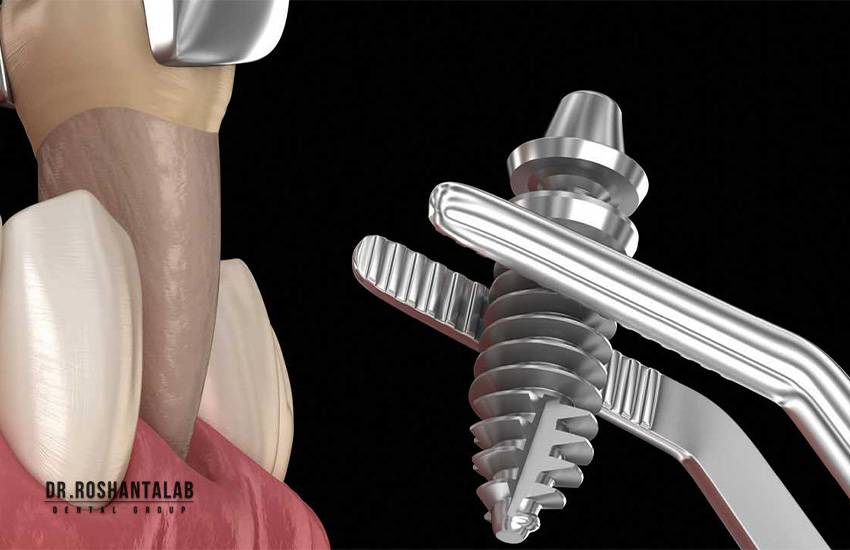

ایمپلنت فوری دندان تکنیکی پیشرفته است که در آن دندان آسیبدیده کشیده شده و همزمان فیکسچر (پیچ تیتانیومی) در استخوان فک کاشته میشود. برخلاف روشهای سنتی، در همان جلسه یک روکش موقت قرار میگیرد تا ظاهر طبیعی حفظ شود. این روش معمولاً ۳ تا ۴ هفته طول میکشد تا روکش دائمی نصب شود. طبق مطالعات، نرخ موفقیت این روش با شرایط مناسب به ۹۵٪ میرسد. آیا این سرعت برای شما جذاب است؟

- کشیدن دندان و کاشت فیکسچر: با بیحسی موضعی، دندان کشیده و ایمپلنت در همان روز نصب میشود.

- نصب روکش موقت: روکش موقت برای حفظ ظاهر و عملکرد قرار میگیرد.

- بهبودی و روکش دائمی: پس از ۳-۴ هفته که استخوان با ایمپلنت جوش میخورد، روکش دائمی نصب میشود.